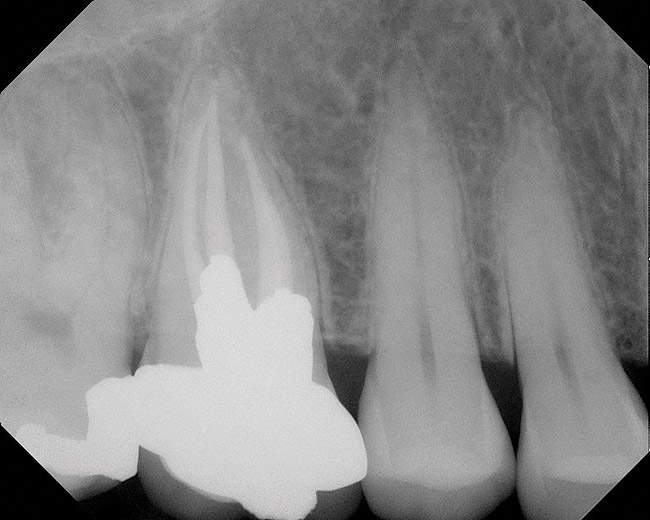

Figure 4  Clinical case of a lack of coronal seal that contributed to the failure of this root canal treatment.

Figure 4

Figure 5  Retreatment of the case shown in Figure 4.

Figure 5